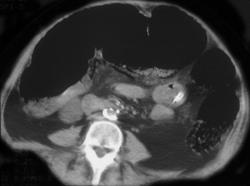

Diverticulitis W/fistulae to Cervix